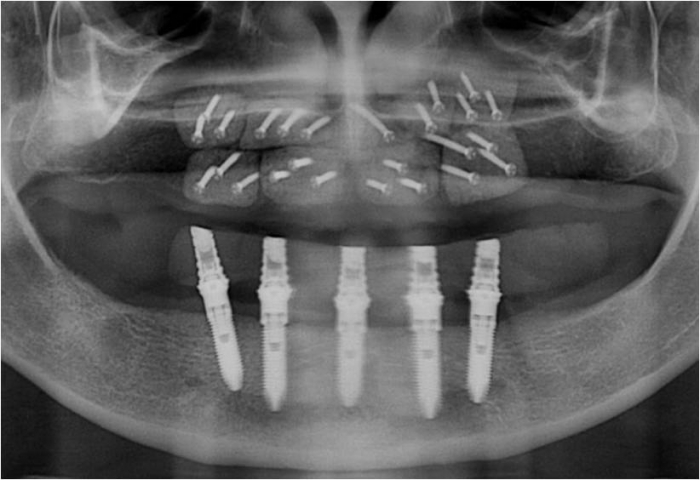

Raio X dos implantes inferiores - Clínica Cliniface

Raio X dos implantes inferiores